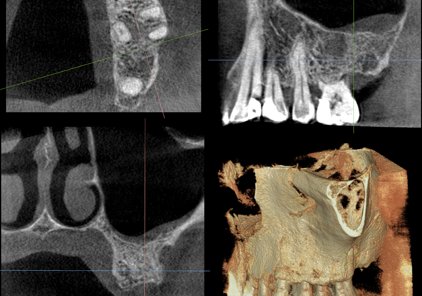

His research interests are mainly focused on improving image quality for Cone Beam CT imaging systems. This is accomplished by reducing image artifacts and better understanding the effects of system’s geometry and reconstruction algorithms. Other areas of research include reporting outputs of AI software in oral radiology and developing frameworks to assess these outcomes in a comprehensive way to ensure fairness and prevent unwanted biases. Finally, Dr. Cobos is very active in the development of novel and creative research methods for any 3D medical or dental imaging modality, including digital formats used in 3D printing and digital dentistry.

Dr. Cobos is actively seeking opportunities to present as a guest speaker in both Research Oriented topics as well as Clinical Presentations (e.g., interpretation of CBCT images).